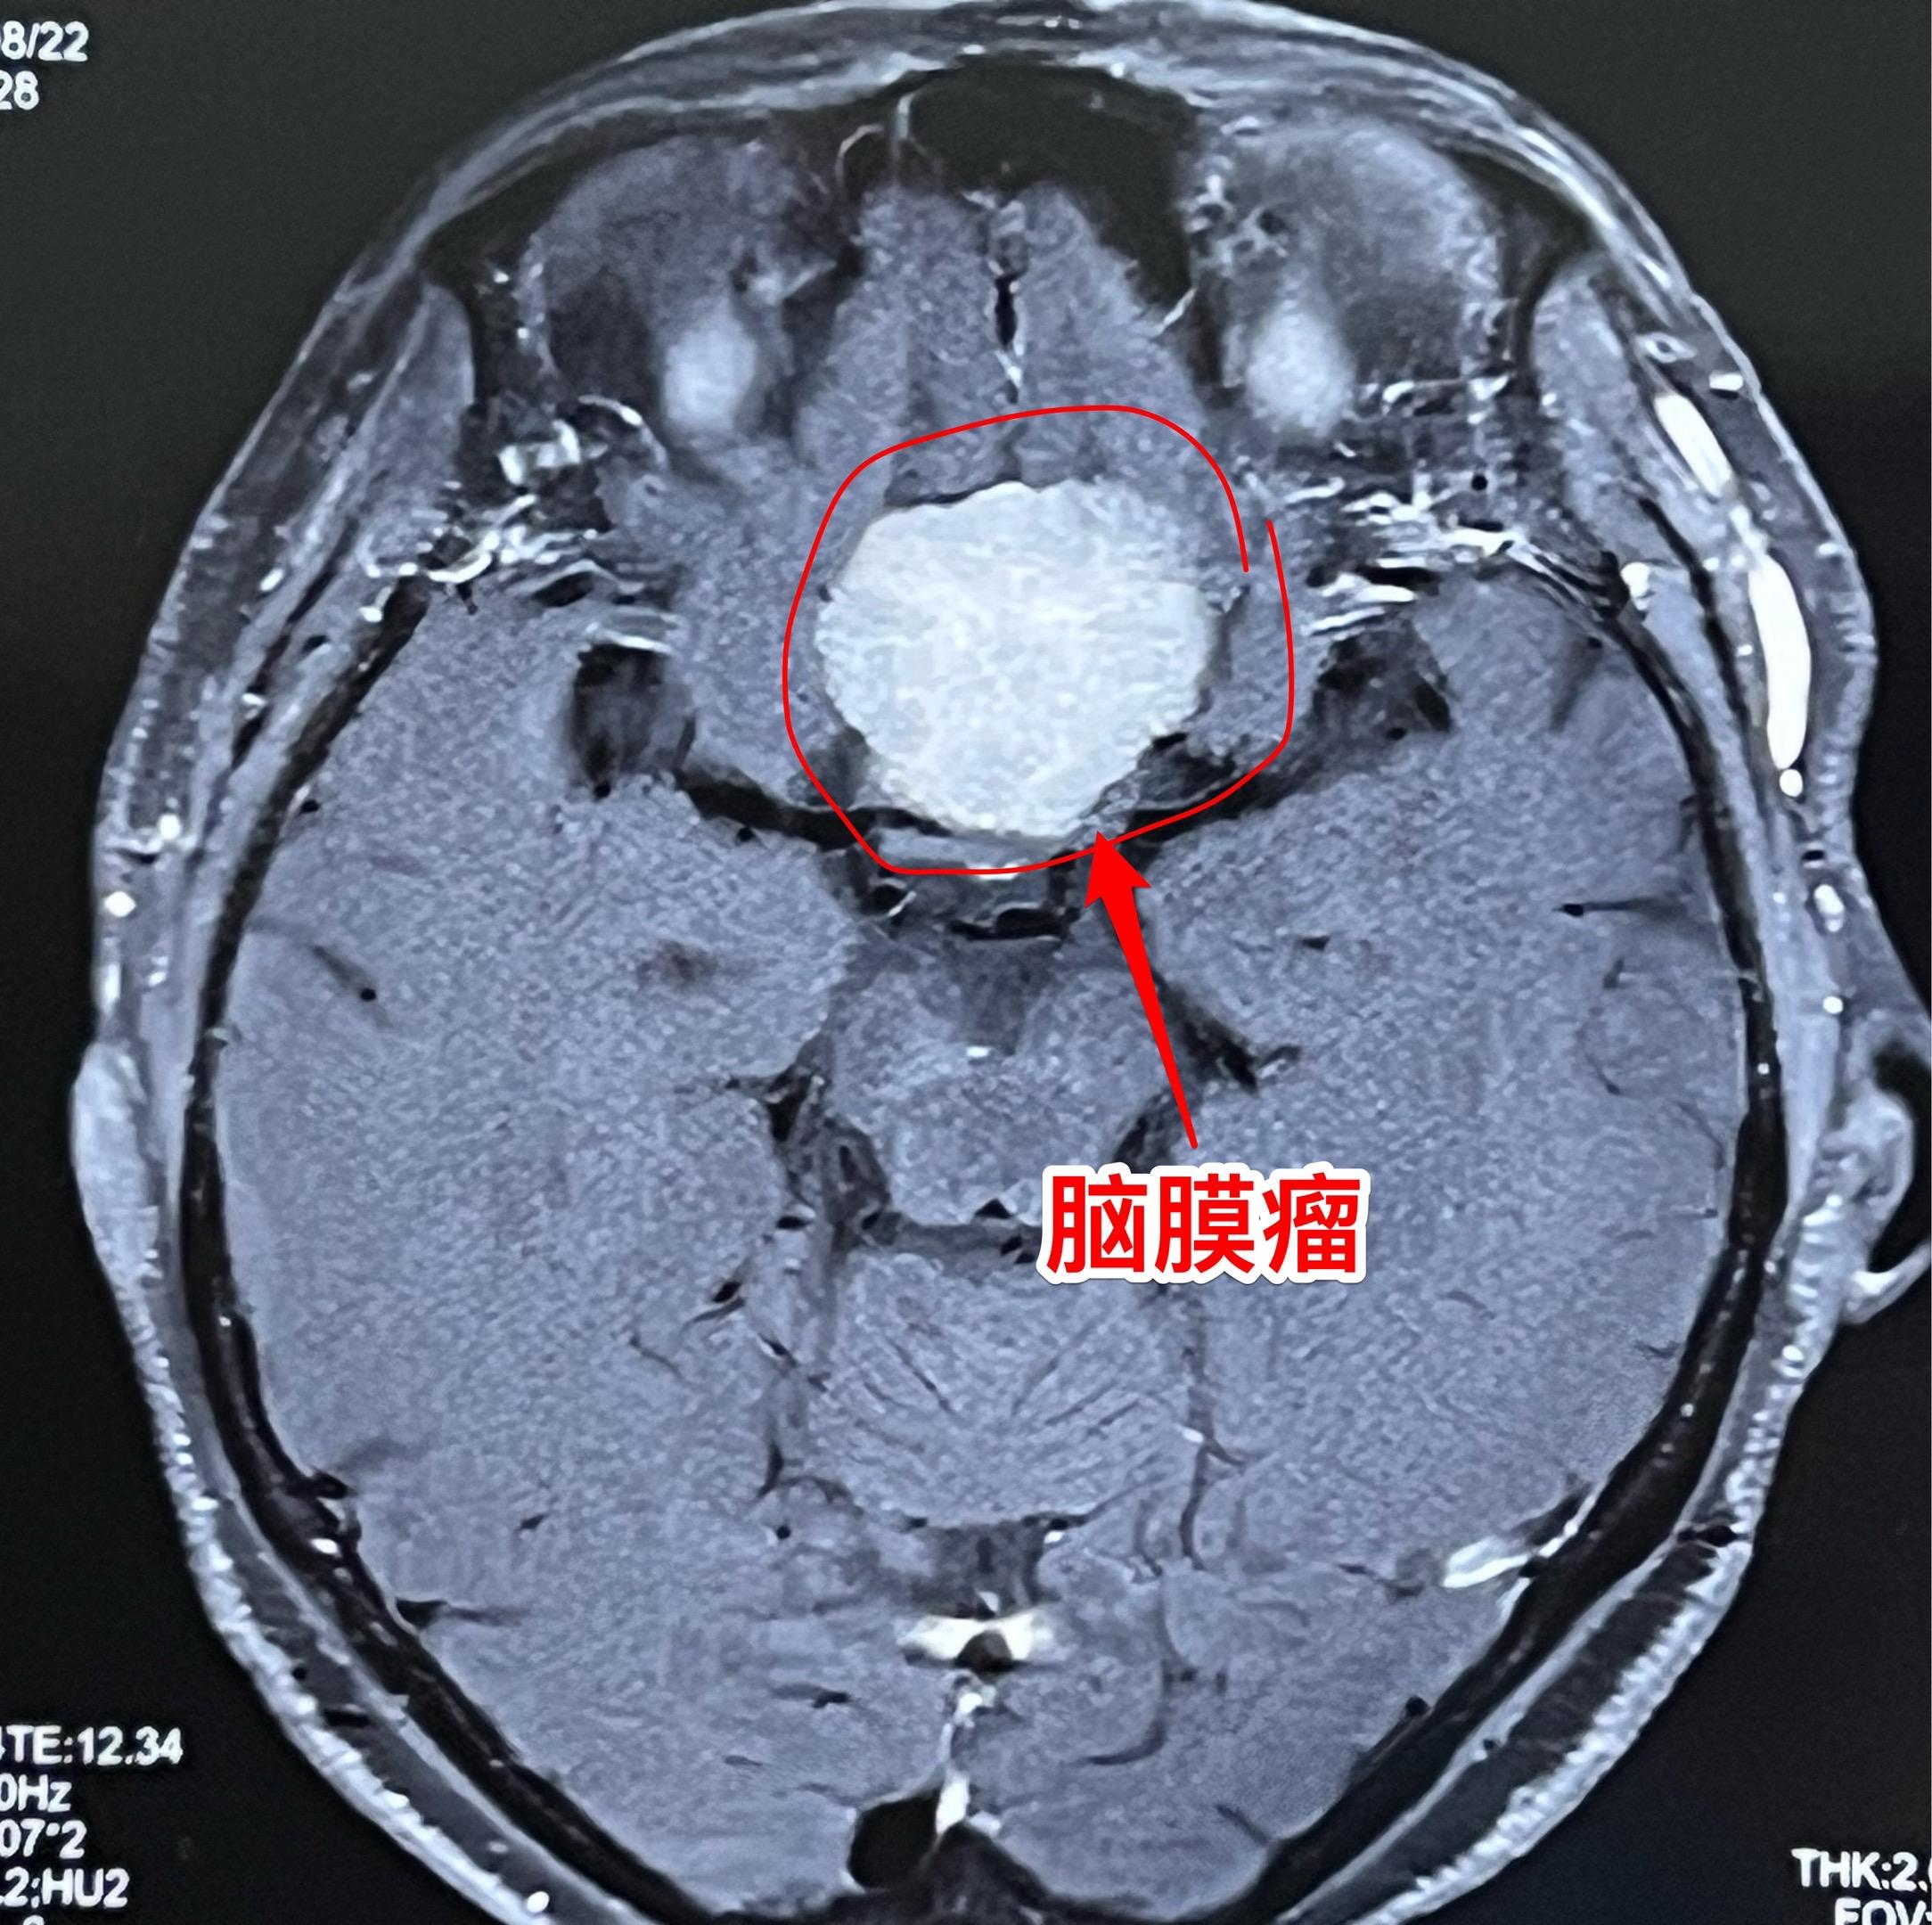

脑膜瘤也会造成视力下降。66岁吉林省女性,退休后喜欢开车到处旅游,并在旅游途中搞直播,拥有三十几万粉丝。 今年她感觉视力明显下降,开车有困难。作了磁共振发现鞍区脑膜瘤,见图。 脑膜瘤属于良性肿瘤,作手术切除肿瘤是最合适的治疗方法。9月16日作了开颅手术,将肿瘤完全切除。手术后病人感视力有改善。脑膜瘤视力下降